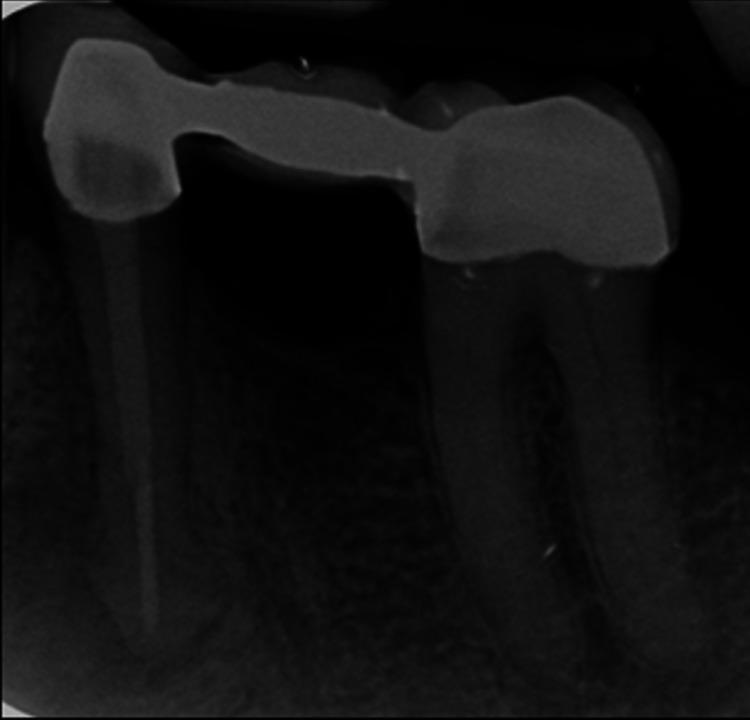

Gingival enlargement may manifest as a side effect of medications (calcium channel blockers, anticonvulsants, or immunosuppressants) and may be associated with inflammation, malignancy, or genetic inheritance. This condition has a significant impact on a patient's quality of life and affects their oral health status. This case report describes the management of a 68-year-old gentleman who presented with generalized gingival enlargement and chronic periapical abscess originating from tooth 34, which served as an abutment for a fixed partial prosthesis. The patient's medical history revealed that felodipine, an antihypertensive medication, was prescribed to him. A comprehensive treatment plan was developed to improve the patient's quality of life.

牙龈增生可能表现为药物(钙通道阻滞剂、抗惊厥药或免疫抑制剂)的副作用,也可能与炎症、恶性肿瘤或遗传因素有关。这种情况对患者的生活质量有重大影响,并会影响他们的口腔健康状况。本病例报告描述了一位68岁男性患者的治疗过程,该患者出现了广泛性牙龈增生以及源自34号牙的慢性根尖周脓肿,34号牙是固定局部义齿的基牙。患者的病史显示,他正在服用降压药非洛地平。制定了一个全面的治疗计划以改善患者的生活质量。